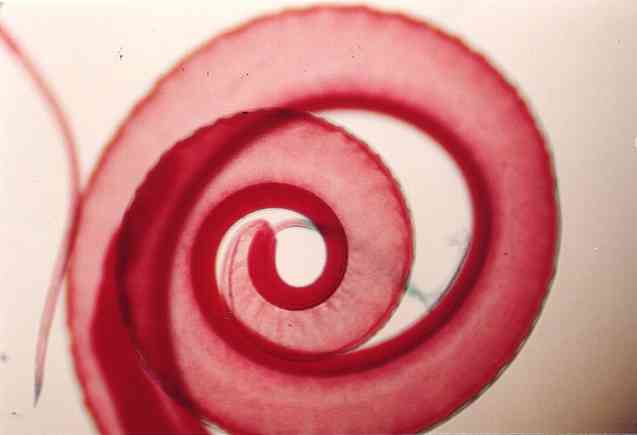

Treponema pallidum merupakan salah satu bakteri anggota filum Spirochaetae. Bakteri ini berbentuk spiral. Terdapat empat subspesies yang sudah ditemukan, yaitu …

Treponema pallidum merupakan salah satu bakteri anggota filum Spirochaetae. Bakteri ini berbentuk spiral. Terdapat empat subspesies yang sudah ditemukan, yaitu …

Karakteristik treponema pallidum, morfologi, habitat / Biologi | Thpanorama - Jadikan diri Anda lebih baik hari ini!

Karakteristik treponema pallidum, morfologi, habitat / Biologi | Thpanorama - Jadikan diri Anda lebih baik hari ini!

Spirokaeta (Spirochaeta) : Pengertian Ciri-ciri Struktur Sel Contoh

Spirokaeta (Spirochaeta) : Pengertian Ciri-ciri Struktur Sel Contoh